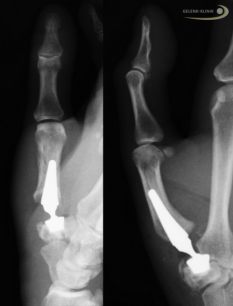

Das Röntgenbild zeigt eine Daumensattelgelenksprothese mit Kugelgelenk. © Gelenk-Klinik

Bei der Daumensattelgelenksprothese wird die Mechanik des Daumensattelgelenks nachgebildet und durch ein Kugelgelenk ersetzt. Die Prothese ist ähnlich aufgebaut wie eine Hüftprothese.